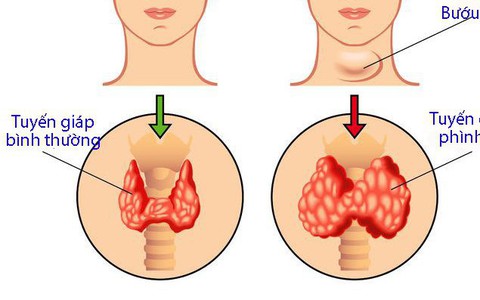

Nếu như bệnh nhân không rơi vào những chỉ định phải mổ bướu thì việc bệnh nhân quyết định mổ là thật sự không nên.